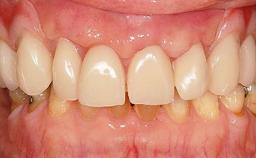

Two dental implants are placed in the same surgical session. The case concludes with the presentation of the final fixed dental prosthesis with a distal cantilever unit.

The 1-year follow-up radiographs demonstrate successful sinus floor elevation and stable bone crest levels around both implants, leading to a favorable long-term prognosis of the implant-supported prosthesis.